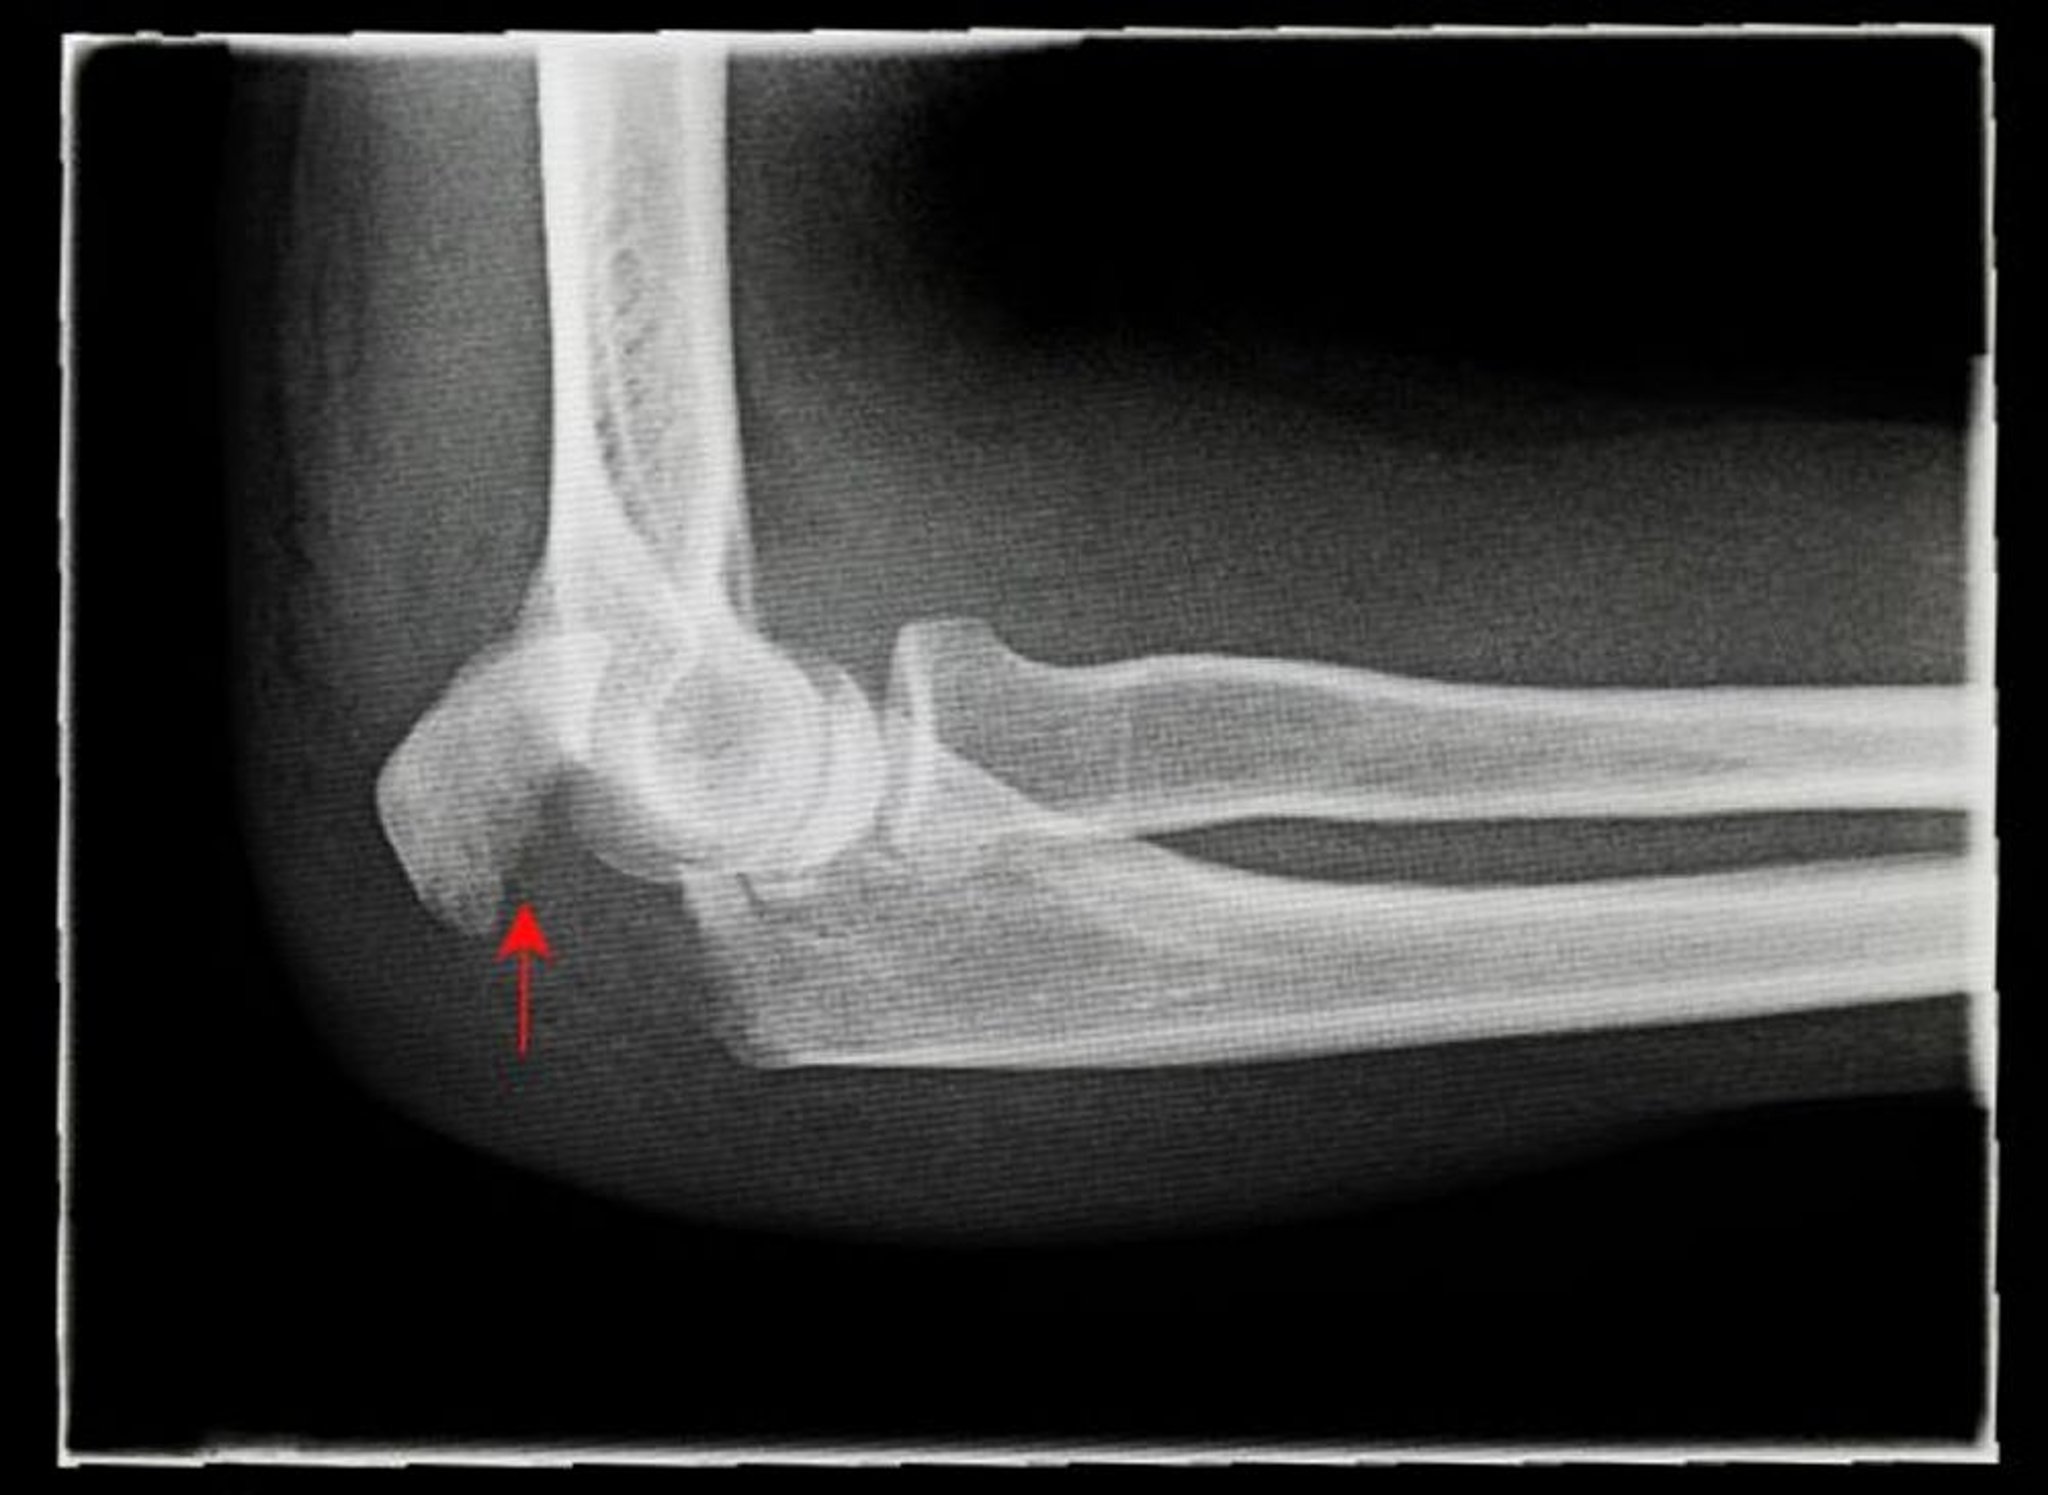

Fracture de l'olécrane

Cette radiographie de profil montre une fracture de l'olécrane déplacée (flèche).